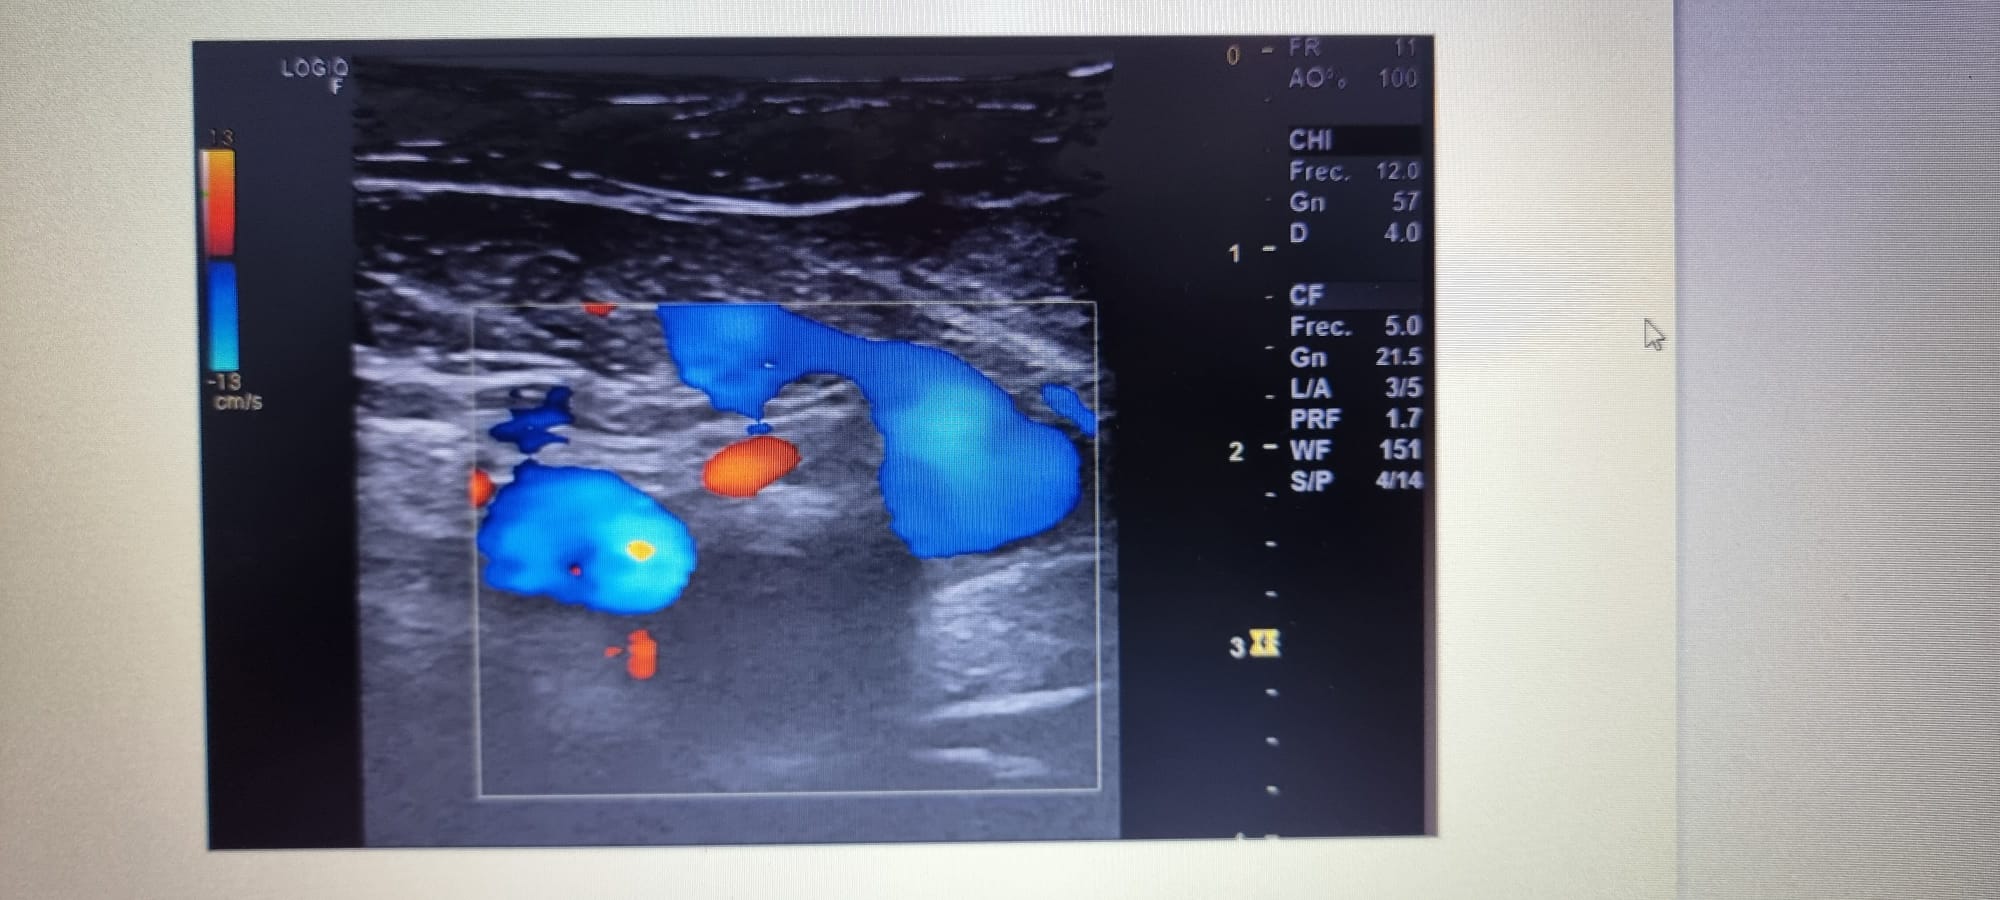

Se realiza ecografia venosa de mid evidenciándose ocupación parcial de femoral común, y segmento de femoral superficial.

Ecografia en Urg hospital: ocupación parcial de la luz de las venas femoral común y segmento proximal de la femoral superficial, ocupación completa de la luz en segmentos medio-distal de la femoral superficial y vena poplitea.